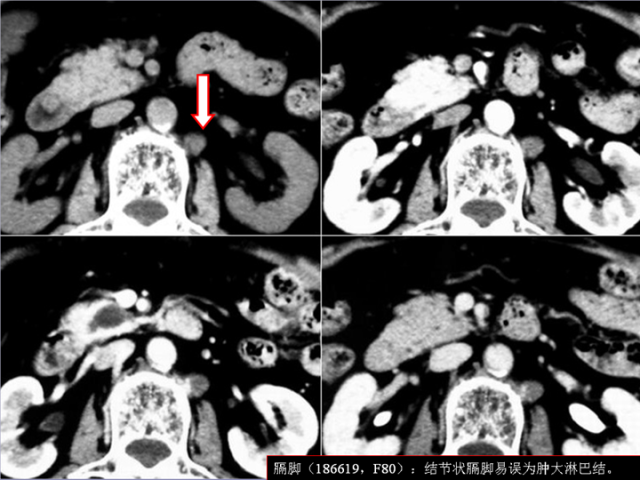

膈肌角解剖及常见变异

作者:王俭 上海长征医院